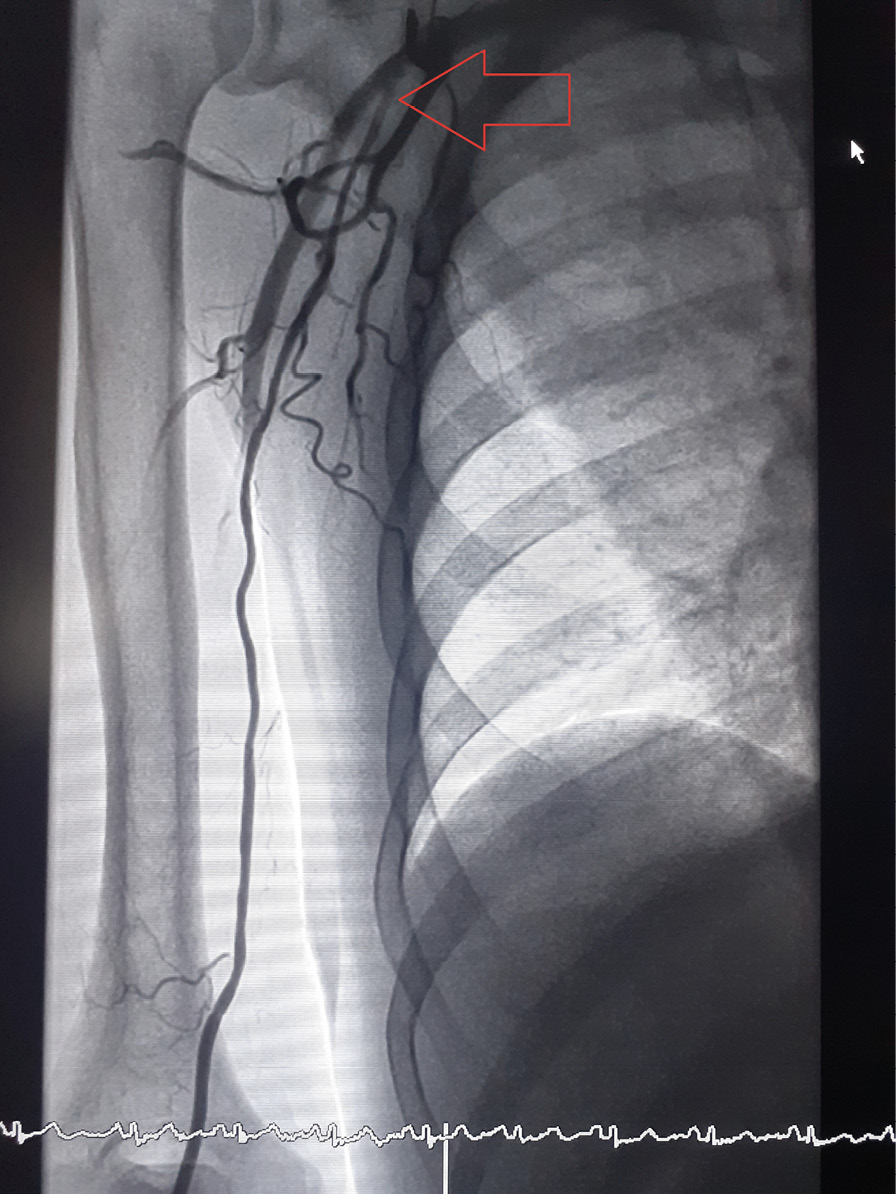

Статистически значимых различий в показателях количества попыток, продолжительности пункции лучевой артерии, времени процедуры, флюороскопии, конверсии у пациентов групп ТРД и ДпЛД выявлено не было (табл. 2). Все 6 случаев конверсии были обусловлены спазмом на этапе пункции или заведения проводника. У 5 пациентов группы ДпЛД был налажен ТРД через лучевую артерию предплечья ипсилатеральной верхней конечности. У 1 пациента группы ТРД для конверсии использовалась лучевая артерия предплечья контралатеральной руки. Конверсий на феморальный доступ не было. Случаев спазма лучевой артерии в процессе процедуры, потребовавшего отказа от доступа, не отмечалось. У 5 пациентов (1 (1%) из группы ТРД и 4 (4%) из группы ДпЛД) наблюдалась аномалия развития: высокое отхождение лучевой артерии (рис. 3), не оказавшее существенного влияния на общую продолжительность процедуры, однако потребовавшее дополнительного введения РКВ для его верификации, тем самым оказав влияние на разницу показателей расхода РКВ в группах ТРД и ДпЛД (195 (150; 400) мл в группе ТРД и 214 (150; 350) мл в группе ДпЛД, p = 0,005). Контрольная артериография лучевой артерии, выполненная после ЧКВ, не выявила случаев перфорации и значимых диссекций. Оценка субъективного комфорта процедуры гемостаза по вербальной описательной шкале оценки боли Gaston-Johansson выявила статистически значимое преимущество ДпЛД перед ТРД (6,4 (4; 10) в группе ТРД и 1,7 (0; 6) в группе ДпЛД, p < 0,001). Частота возникновения гематом 3-й степени по шкале EASY была статистически значимо выше в группе ТРД, отмечено пятикратное превышение данного показателя по сравнению с группой ДпЛД (15 (15%) пациентов в группе ТРД против 3 (3%) пациентов в группе ДпЛД, р = 0,004) (табл. 3). Гематом 4-й степени по шкале EASY в группе ДпЛД выявлено не было, тогда как в группе ТРД они возникли в 4 (4%) случаях. Гематомы 5-й степени по шкале EASY не регистрировались ни в одной из групп.

Рис. 3. Аберрантная лучевая артерия, отходящая от подмышечной артерии (уровень отхождения указан красной стрелкой)